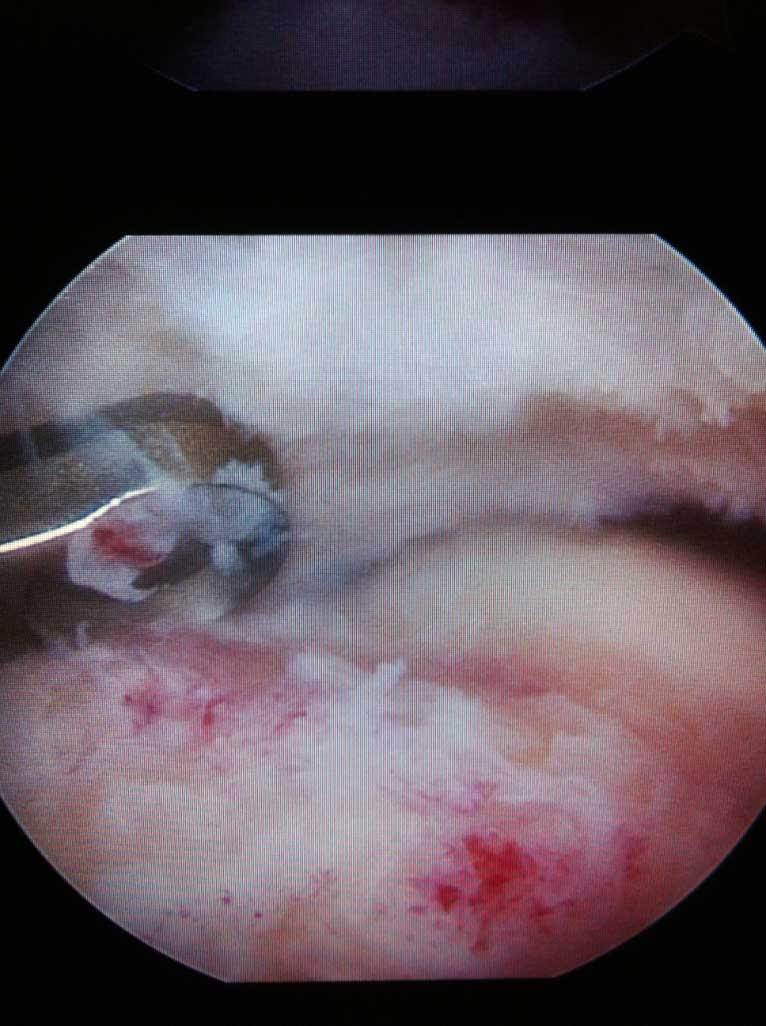

Die s.g. Tendinitis calcarea ("Kalkschulter") ist sehr häufige Ursache von akuten aber auch chronischen, manchmal ausgeprägten Schulterschmerzen.

Lässt sich die Schmerzsymptomatik durch konservative entzündungshämmende Therapie nicht lindern, so wird eine arthroskopische Kalkdepotausräumung empfohlen. Dabei, innerhalb 20-30 min wird das Kalkdepot aus der Schultersehne durch 3-5 kleinen Stichinzisionen entfernt und die Sehne anschliessend genäht. Die Nachbehandlung beträgt zirka 8-10 Wochen mit Krankengymnastik und ggf. anschließender Reha Maßnahme.